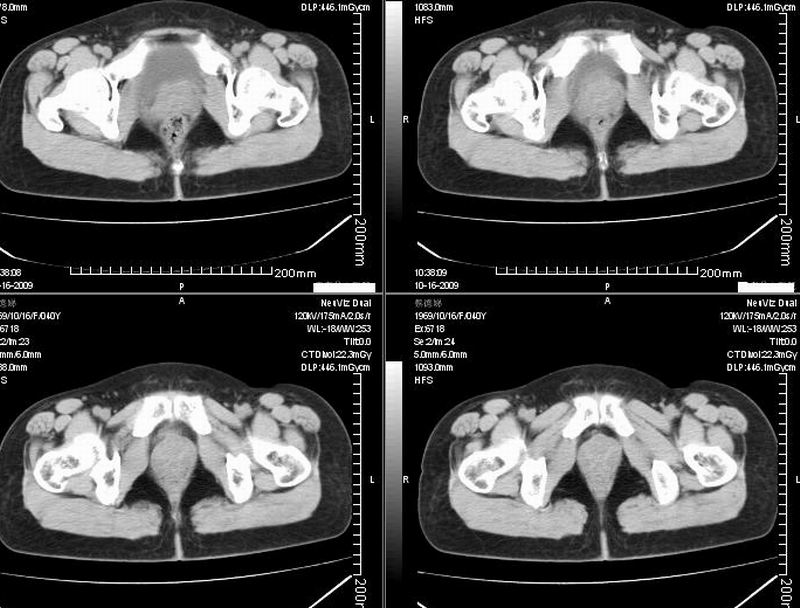

女:40y:下腹隐痛1周+,无其它不适,这个子宫会太一点吗?有临床意义吗?

宫腔内有积液,考虑炎症可能

形态不规则,不能除外肌瘤可能。

子宫偏左,略显增大,期内可见低密度改变,考虑宫腔积液可能。

子宫偏左,略显增大,期内可见低密度改变,考虑宫腔积液可能。 不能除外肌瘤可能。

子宫体积稍增大,其内见低密度影。考虑宫腔积液可能。

子宫不规则的增大 宫腔内积液 有多种考虑

1 子宫肌瘤

2 子宫腺肌症

3 子宫内膜炎

4 月经期 (宫腔内积血)